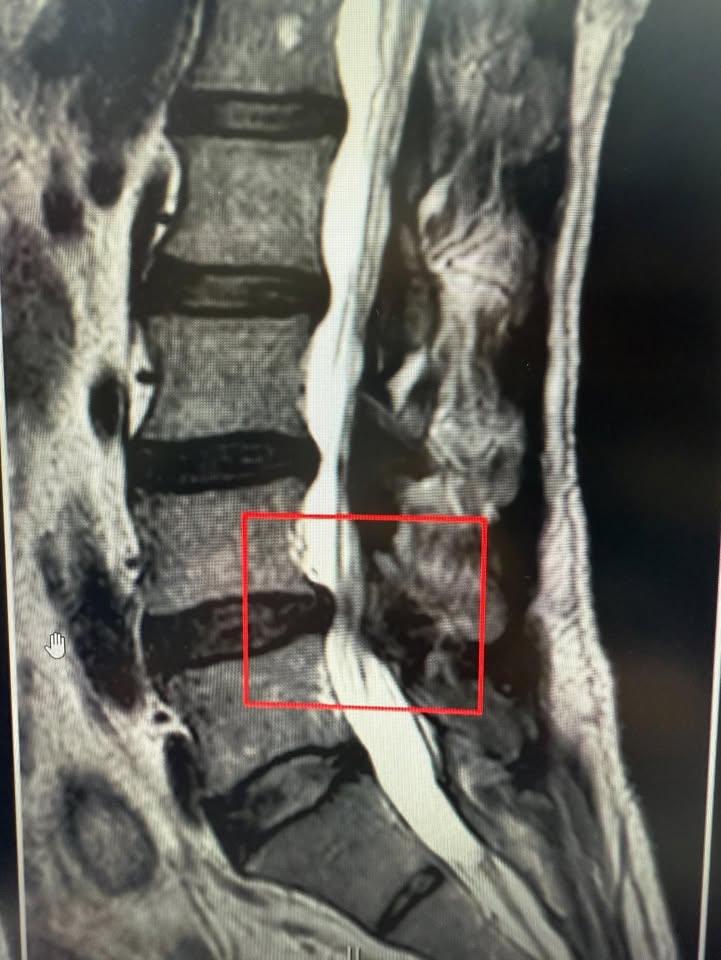

Cervical Spine Treatment Cases 精彩回顧 患者高爾夫球影片親自見證 2025.01.17 椎管狹窄曾經很難很難的病也有一線曙光 2025.01.19 2025.01.20 27歲陳小姐的巨大椎間盤突出康復之路 2025.01.23 2025.01.30 嚴重腰椎滑脫與椎管狹窄的重生之路 2025.02.05 嚴重心悸伴隨視力模糊跟血壓飆升 2025.02.07 頸椎脊髓壓迫導致手麻跛行掰咖 2025.02.11 椎間盤突出合併椎管狹窄的奇蹟之旅 2025.02.12 巨大椎間盤突出治療醫案 2025.02.13 擺脫腰痛束縛原來是椎間盤突出 2025.02.18 L小姐的交感神經症候群從痛苦折磨到重生 2025.02.19 半年無法站立原來是椎間盤巨大突出 2025.02.21 2025.02.23 2025.02.25 ← 上一頁 28 29 30 31 下一頁 →